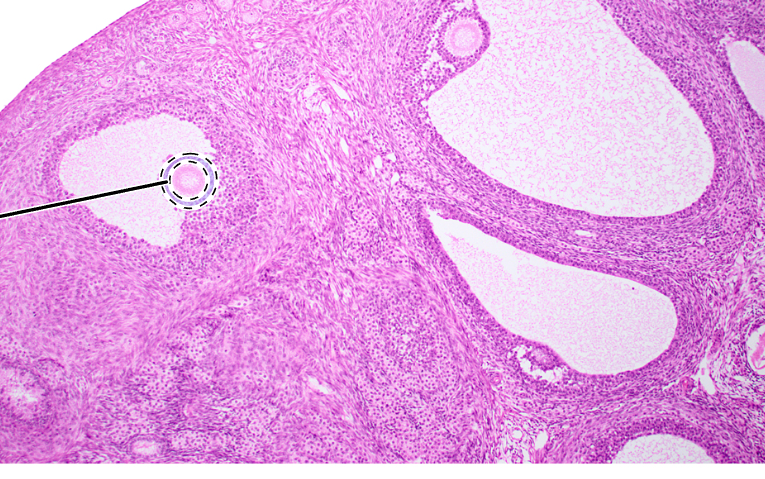

ovary (sagittal section)

primordial follicles

antrum

corona radiata

oocyte

mature tertiary follicle

zona pellucida